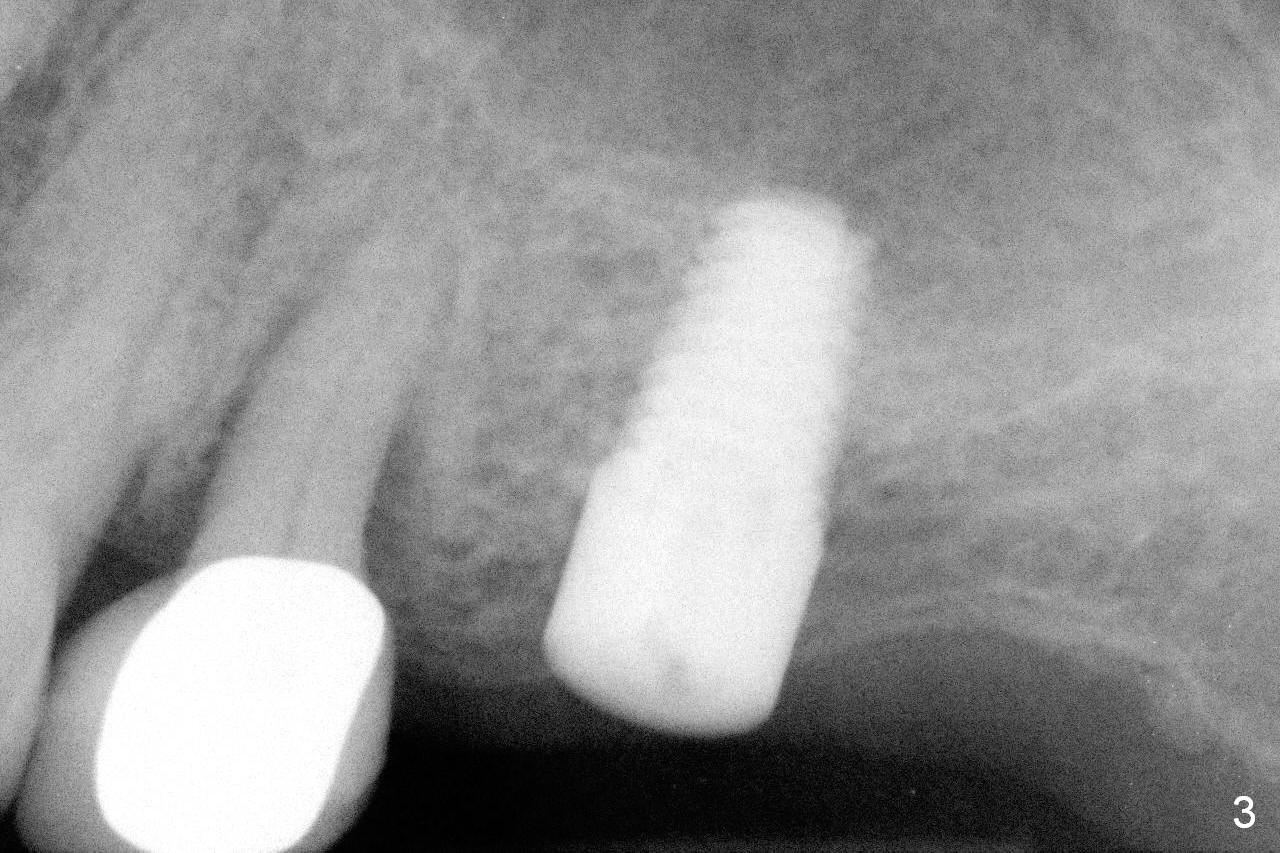

A 73-year-old woman is a possible bruxer with partial edentulism; the tooth #13 had increased periodontal ligament (pdl) space 4 years ago (Fig.1 *). A 5x14 mm tissue-level implant is placed at the site of #14 (Fig.2). The implant appears to be osteointegrated in 6 months (Fig.3). There is crestal bone loss 8 months post cementation (Fig.4 *). The persistent increased pdl at #13 is most likely associated with occlusal tramua from the tooth #19 (Fig.5 (13 months post cementation of #14)). Three years post #14 cementation, the tooth #13 has mobililty II (Fig.6); bone density increases around the apical half of the implant (arrowheads). Normally bone density is the highest coronally where functionality dictates. This indicates the bone loss is getting worse at #14 as well.